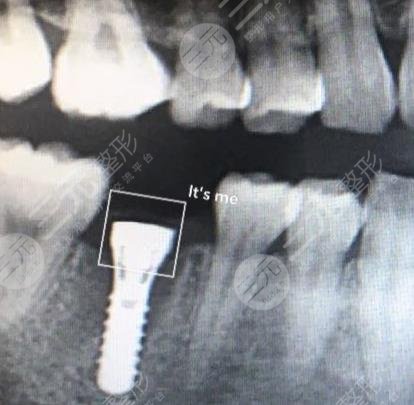

Surgical Procedure: Dental Implants

Since dental implant surgery can fill in the missing tooth and make the whole oral condition look more harmonious and natural, in order to make it more aesthetically pleasing, I agreed to this treatment. Under the guidance of a professional doctor, the oral cavity was cleaned and disinfected in a timely manner, and the missing parts were also punched, and then the implants were placed, then the abutment, and then the crown, the whole process took several months of the world, the dental implant surgery went relatively smoothly, and the whole process did not have any medical accidents, which was relatively easy for me, and the treatment was completed.